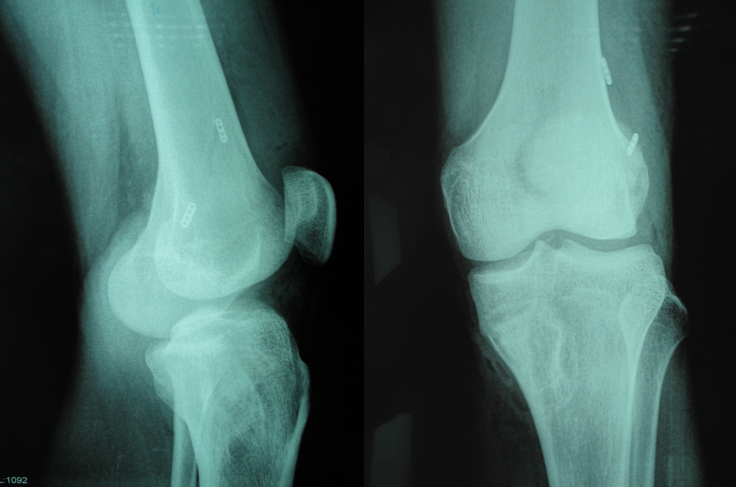

重建术后X片